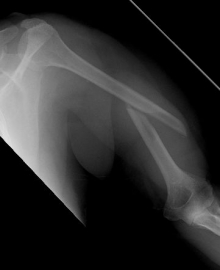

Proximaler Oberarmbruch3Proximaler Oberarmbruch4

Picture: The subcapital humeral fracture shown here in the axis is not broken and only slightly bruised, so that a conservative therapy is possible. The left image shows the follow-up after 3 weeks. The patient has already started physiotherapy. The x-ray shows an increase bone healing.